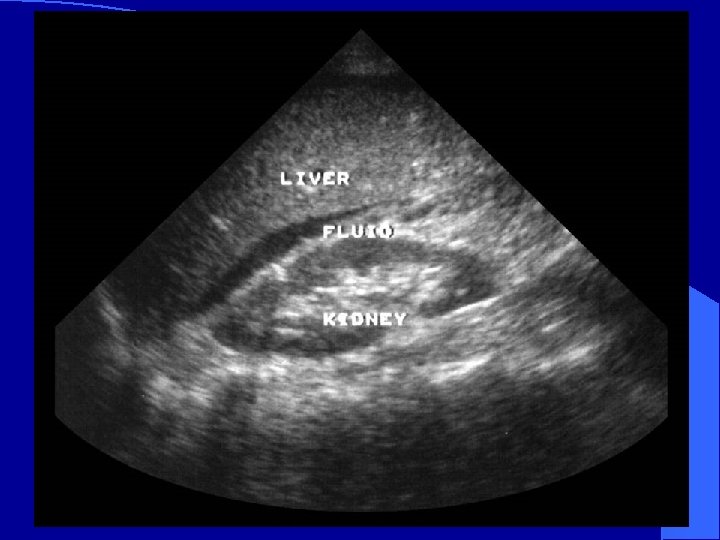

RUQ l Image on screen: – Liver cephalad – Kidney inferiorly – Morison’s Pouch*: space between Glisson’s capsule and Gerota’s fascia * *

Normal RUQ l Image kidney – Longitudinally – Transversely l Two toned structure – Cortex/medulla – Renal sinus

Appearance of blood l Fresh blood – Anechoic (black) l Coagulating blood – First hypoechoic – Later hyperechoic

Normal Morison’s Pouch Free fluid in Morison’s Pouch